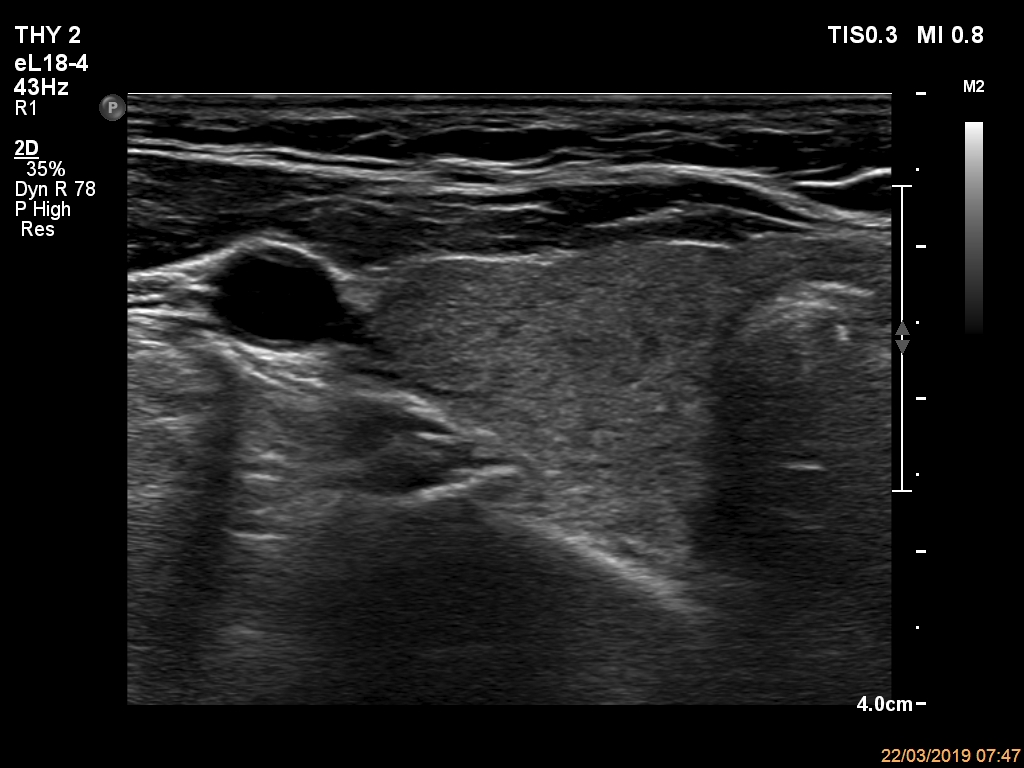

Ultrasonography. The thyroid was echonormal and had multiple nodules. The only lesion of a possible oncological importance was in the left lobe. It was hypoechoic. The dimensions were 16x14x23 mm (width, depth, length, respectively). The lower border presented an undulation which was caused by another, hyperechoic nodule. The nodule presented a predominant perinodular blood flow and had an average rigidity on elastography.

The nodule in the left lobe illustrates non-pathological form of lobulated margins.